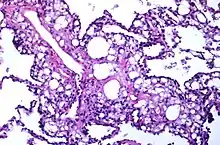

Numerous interstitial fat globules of varying size accompanied by inflammation and fibrosis is characteristic of chronic lipid pneumonia secondary to lipid aspiration.

Once inhaled, these fuels induce an inflammatory reaction in lung tissue. They are not metabolized by tissue enzymes, but undergo emulsification and become engulfed by macrophages which, with time, may disintegrate and release oily substances surrounded by fibrous tissue and giant cells.[8]